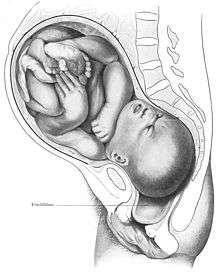

The vagina provides a channel to deliver a newborn to its independent life outside the body of the mother. When childbirth (or labor) nears, several symptoms may occur, including Braxton Hicks contractions, vaginal discharge, and the rupture of membranes (water breaking).[55] When water breaking happens, there may be an uncommon wet sensation in the vagina; this could be an irregular or small stream of fluid from the vagina, or a gush of fluid.[56][57]

When the body prepares for childbirth, the cervix softens, thins, moves forward to face the front, and may begin to open. This allows the fetus to settle or "drop" into the pelvis.[55] When the fetus settles into the pelvis, this may result in pain in the sciatic nerves, increased vaginal discharge, and increased urinary frequency. While these symptoms are likelier to happen after labor has already begun for women who have given birth before, they may happen approximately ten to fourteen days before labor in women experiencing the effects of nearing labor for the first time.[55]

The fetus begins to lose the support of the cervix when uterine contractions begin. With cervical dilation reaching a diameter of more than 10 cm (4 in) to accommodate the head of the fetus, the head moves from the uterus to the vagina.[55] The elasticity of the vagina allows it to stretch to many times its normal diameter in order to deliver the child.[19]

Vaginal births are more common, but there are sometimes complications and a woman might undergo a caesarean section (commonly known as a C-section) instead of a vaginal delivery. The vaginal mucosa has an abnormal accumulation of fluid (edematous) and is thin, with few rugae, a little after birth. The mucosa thickens and rugae return in approximately three weeks once the ovaries regain usual function and estrogen flow is restored. The vaginal opening gapes and is relaxed, until it returns to its approximate pre-pregnant state by six to eight weeks in the period beginning immediately after the birth (the postpartum period); however, it will maintain a larger shape than it previously had.[58]